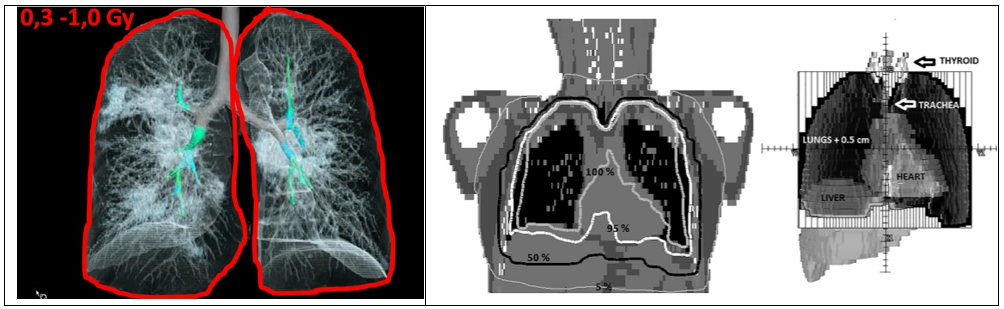

Stadiul I este cel viral, stadiul II (IIA și IIB) cel pulmonar (apariția infiltratelor pulmonare) și stadiul III cel de hiperinflamație însoțit clinic de starea de insuficiență respiratorie. Tratamentul radiologic poate fi efectuat prin aplicarea unei doze minimale unice de 0,3-1,0 Gy la nivelul întregului parenchim pulmonar.

Radioterapia cu doza redusa trebuie efectuată în faza IIa sau IIb a ciclului bolii (figura 3) astfel că intrarea în faza a III-a să nu aibă loc sau, dacă are loc, procesul inflamator la nivelul parenchimului pulmonar să fie mult atenuat de iradierea aplicată și fibrozarea să nu mai fie accentuată.

Figura 3. Aplicarea radioterapiei în funcție de stadiul clinic al infecției.

Săgeata roșie indică faza în care este indicată iradierea pulmonară

Tehnicile de radioterapie aplicate sunt: câmpuri opuse aplicate direct pe masa de iradiere. Doze de 0,3 până la 1 Gy pot fi aplicate într-o singură ședință de iradiere, durata întregului act terapeutic fiind de 30 minute (figura 4).

Figura 4. Reconstrucția 3D a unui plămân afectat de SARS-CoV-2. Vizualizarea zonelor inflamate și a câmpurilor (marcate cu roșu) de iradiere pulmonară cu doză redusă (stânga). Planul de iradiere și realizarea tehnică efectuată de echipa lui Trinidat-Hernadez (dreapta). Sursa: Radiotherapy & Oncology, decembrie 2020, vol 153: 289-295.